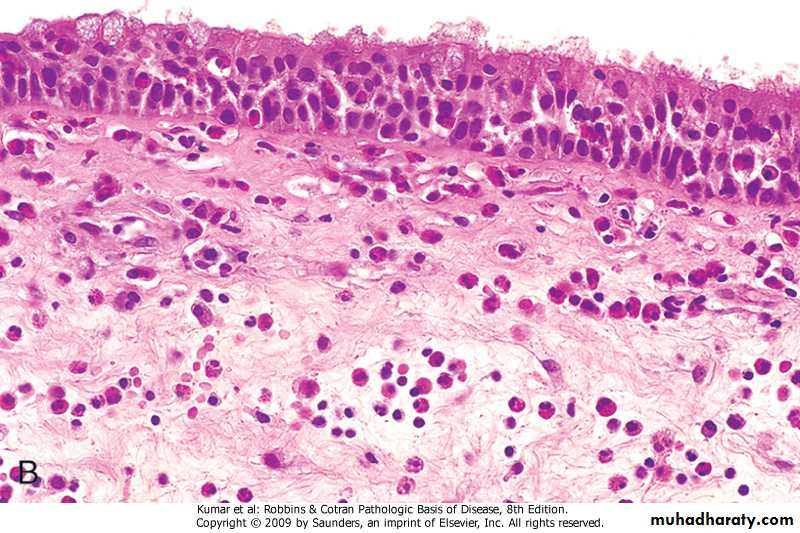

Bronchial Asthma : Pathology

Gross: The lung are overinflatedMicroscopical:

1.The lumen of the bronchi and bronchiole contain thick mucus plug (containing whorls of epithelium called curschmann spirals),charcot leyden crystals and eosinophils

2. The basement membrane shows characteristic hyaline thickening

3. The submucosa shows congestion . edema and infiltration by eosinophils & mast cells

4. The bronchial muscle are hypertrophied

Bronchial mucosa in Asthma